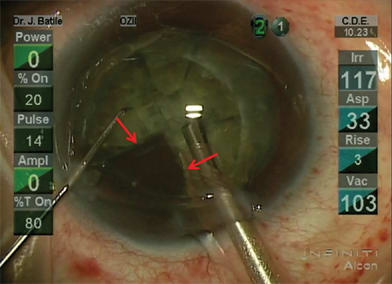

The femtosecond laser enables precise cuts that have important safety and performance implications both peri-operatively and long term. Integrated imaging systems, such as on-board OCT, provide registration to direct the laser both laterally and in depth (Figure 1). For clear corneal incisions, the OCT can provide the corneal thickness at the desired incision location so the architecture for incisions can be properly customized for each patient (Figure 2). This can include the main cataract incision sized for surgical instrumentation, such as the phaco tip and lens injector, and is designed for a watertight seal. It can also include side port incisions. The depth and architecture for relaxing incisions can also be registered, calculated and accurately delivered on the desired axis.

Figure 2. Clear-corneal incision made by the femtosecond laser (red arrows) with perfect tongue and groove apposition of edges of the incision).